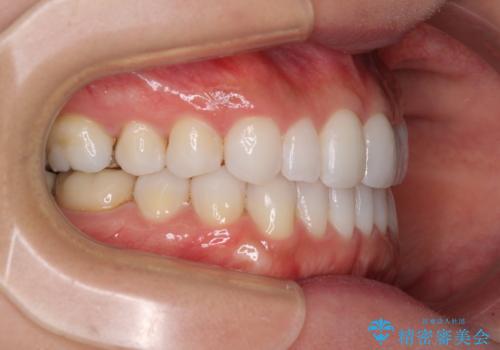

軽度の叢生をインビザライン・ライトで解消

- 前歯が気になるとのことで来院された患者様です。

歯列不正は軽微であったため、インビザライン・ライトにより、費用を抑えて矯正治療を行うこととしました。

短期間で気になる前歯の歯列を改善することができました。